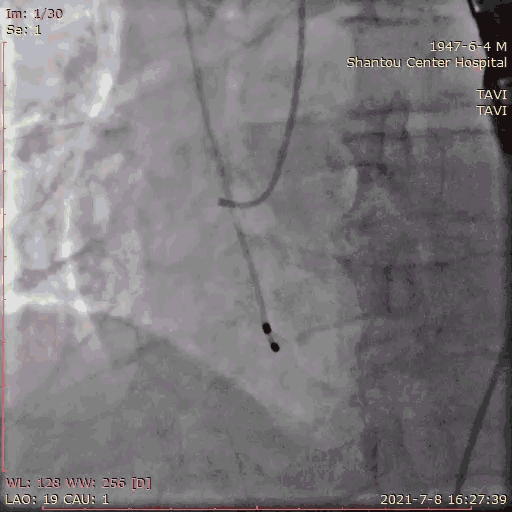

跨瓣

180bpm起搏后打球囊,造影,撤球囊,停起搏;23球囊预扩后无漏,冠脉通畅,选择29瓣膜。

球囊预扩张